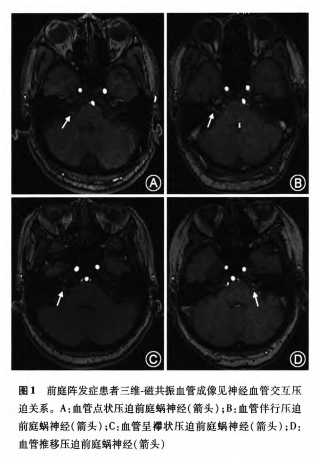

前庭阵发症16例临床特征分析

1449x1980 - 832KB - PNG